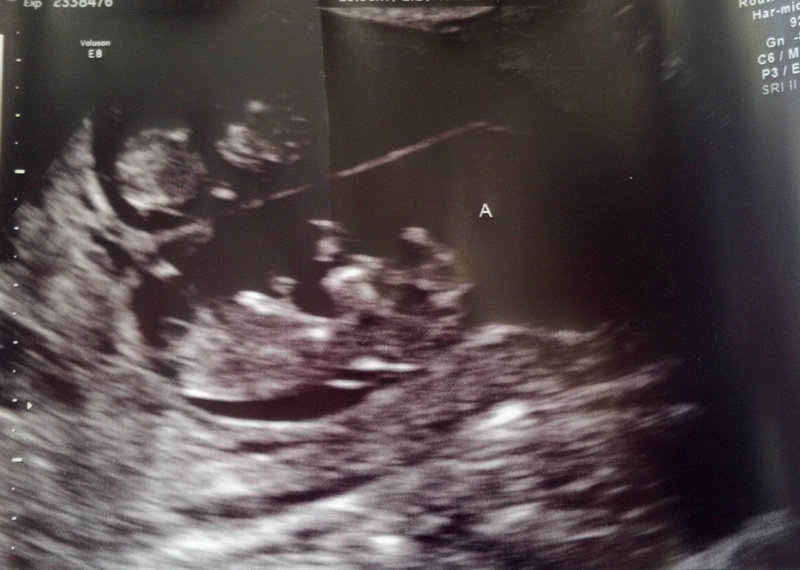

BABY A

Attachment 3157